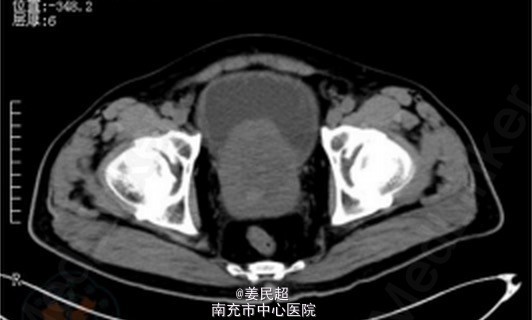

因患者一般情况良好,各项生命体征平稳,无明显腹胀、腹肌紧张,故降低冲洗速度,继续修整切除前列腺尖部增生腺体。术后留置导尿、缓慢膀胱冲洗。术后CT检查显示膀胱前壁有一破裂口,位于腹膜外(图2)。患者恢复良好,10d后拔除导尿管,自行排尿通畅。 气体爆炸与爆炸性气体在膀胱内聚集有关。电切过程中由于高温电灼、组织碳化,组织受热分解产生以氢气为主的混合性气体。膀胱内气体爆炸可以无明显膀胱损伤,也可出现膀胱黏膜撕裂、腹膜外或腹膜内膀胱破裂甚至合并肠管损伤等严重并发症。术中闻及气体爆炸声后,必须立即停止操作,仔细检查膀胱损伤情况。膀胱损伤轻微或虽有腹膜外膀胱破裂但破裂口较小时,可根据患者当时情况决定是否继续手术,术后保持膀胱空虚状态使其愈合。若破裂口较大、多处破裂、伴有活动性出血或腹膜内膀胱破裂时,需立即改开放性手术进行膀胱修补等处理。